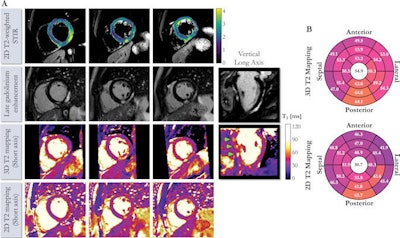

The researchers compared the reproducibility of their 3D whole-heart free-breathing technique with 2D breath-hold T2 mapping in phantoms as well as eight healthy participants. They also investigated its clinical performance in 25 patients with suspected myocarditis.

Using the 3D T2 mapping technique, the researchers found that patients with suspected myocarditis had prolonged myocardial T2 values (68 msec ± 7) in comparison with participants without a history of heart disease (51 msec ± 3).

In 21 of the 25 patients, interpretations were the same between the two methods. However, in four (16%) cases, cardiac inflammation was found to be present with high confidence on the 3D T2 mapping images but deemed to be inconclusive on the corresponding 2D T2 mapping images.